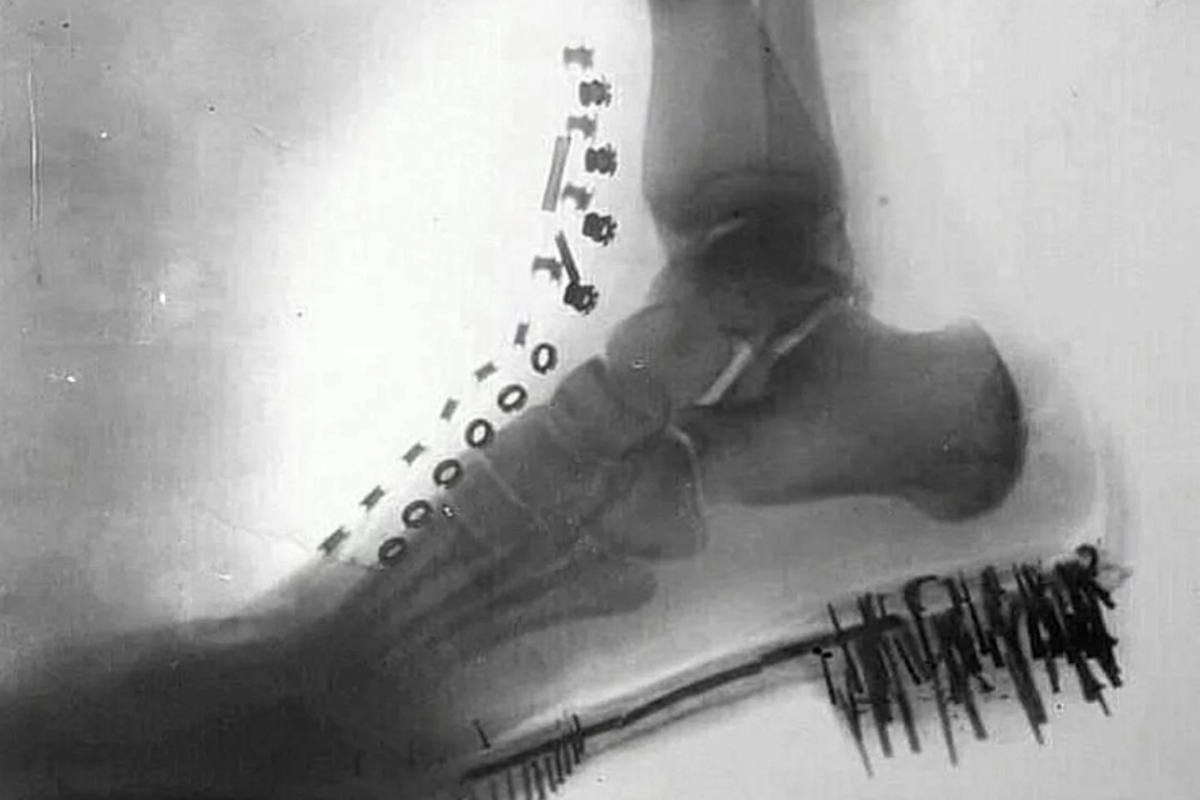

Nikola Tesla hizo algo que aún hoy impresiona cuando se habla de tecnología y ciencia. En 1896, ya estaba produciendo imágenes radiográficas de su propio pie y de su propia mano, pocos meses después del anuncio oficial del descubrimiento de los rayos X por Wilhelm Conrad Röntgen, en noviembre de 1895.

Tesla utilizó bobinas de alta tensión y tubos de descarga a vacío desarrollados por él para generar las imágenes. El resultado fue la producción de radiografías de su propio pie y de su propia mano aún en 1896.

Además del costo, el nivel técnico era extremo: los experimentos involucraban tensiones superiores a 100 mil volts, algo considerado muy avanzado para finales del siglo XIX.